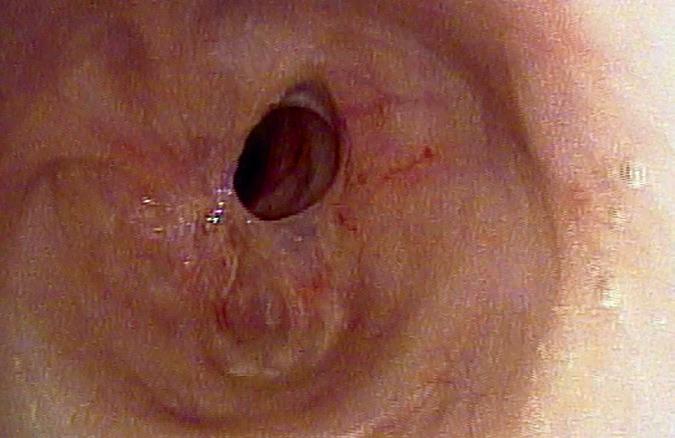

A 70-year-old man who had undergone postauricular underlay myringoplasty to treat chronic otitis media 10 years earlier presented with a 6-month history of hearing impairment, aural fullness, and occasional otorrhea of the right ear. Otoscopy revealed a large, bulging mass on the posterosuperior aspect of the external auditory canal (EAC); the tympanic membrane was invisible (figure 1). Computed tomography of the temporal bone revealed a right-sided, 2 × 2-cm soft-tissue mass in the EAC, with erosion of mastoid air cells but a normal eardrum and middle ear cavity.

Figure 1. Otoscopy displays a large, bulging mass in the posterosuperior aspect of the external auditory canal.

A total of 30 patients (17 men and 13 women) (32 ears) with a mean age of 52 years (range: 20 to 74) were enrolled. The mean number of previous tympanoplasties was 1.18 (range: 1 to 3); perforation size was small in 14 (43.8%) ears, medium in 13 (40.6%) ears, and large in 5 (15.6%) ears, and included 2 total perforations. The average preoperative air-bone gap was 19.4 ± 7.6 dB. The mean follow-up time was 7 months (range: 1 to 45), and the overall surgical success rate was 93.3%. An image obtained 9 months postoperatively is shown in figure 2.